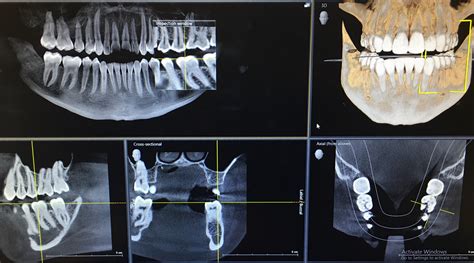

AI Software Will Soon Automatically Fix Any Dot In Incorrect Place Dental Xray

Dental Xray Units at Robin Alexander blog